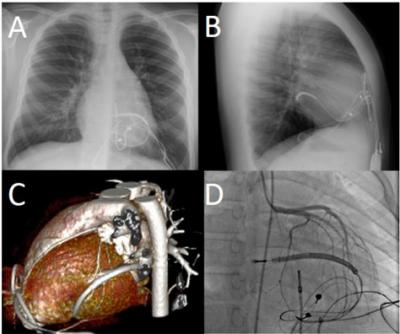

image: Images of the different imaging techniques used to diagnose one of the patients who displayed symptoms. Chest x-ray in the posterioranterior (A) and lateral (B) projections, showing the classic pattern of cardiac strangulation from epicardial leads, as the ICD lead courses leftward and posterior around the heart. Computed topography (C) shows the ICD lead constricting the left ventricle and obtuse marginal branch of the circumflex artery. Catheter angiography (D) shows loss of contrast within the obtuse marginal branch as it courses below the ICD lead.

The sudden death of a child with an epicardial pacemaker following coronary artery compression prompted investigators to enhance surveillance of all patients with epicardial pacing or defibrillation systems. They reviewed the records of all patients followed at Boston Children's Hospital from 2000-2017 who had either active or abandoned epicardial wires that included coronary imaging, either by computed topography (CT) scan or catheter angiography through the vessels in the leg. Of 145 patients, eight (5.5 percent) exhibited some degree of coronary compression from their epicardial leads. Six of these patients displayed symptoms; in addition to the case of sudden death, there were three cases of chest pain and two cases of unexplained fatigue. As a result of the review, seven patients underwent surgical removal or repositioning of their epicardial leads.

This study helps provide a framework for monitoring patients with epicardial pacemakers or defibrillators and identifying those who may need revision or removal of their epicardial wires. Dr. Mah and colleagues compared three screening techniques. They recommend that pediatric patients with epicardial devices should get screening chest x-rays every few years to assess how their wires look in relation to their heart, as the positioning may change as the child grows. They found that chest x-ray had a high specificity and was a good screening tool, easy to perform, inexpensive, and non-invasive. However, it can produce some false-negatives even when patients were symptomatic.

The authors propose that patients with concerning chest x-rays, symptoms such as unexplained chest pain or tiredness, or evidence of heart muscle damage or dysfunction should ideally have a cine CT scan that can image the heart moving in relation to the epicardial wires. Although this can also result in a false-positive, CT is less risky for pediatric patients because radiation doses are now much lower for this non-invasive imaging method.

If cine CT is not available, they advocate that patients undergo catheter angiography to confirm the diagnosis before taking a patient to surgery.